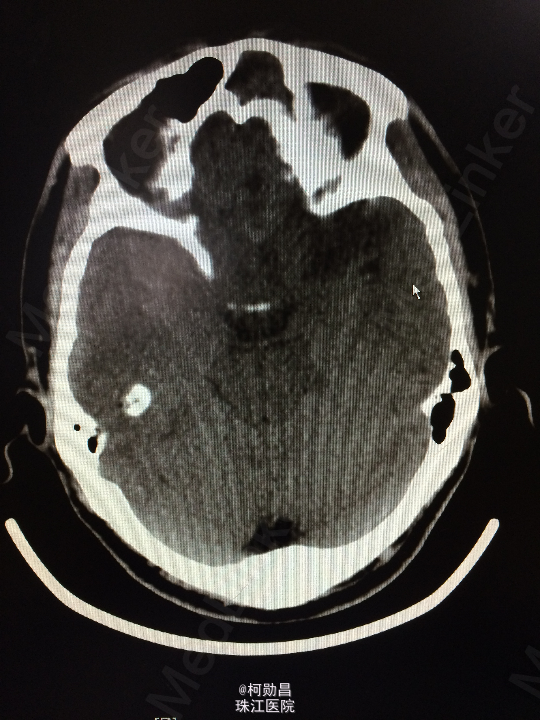

主诉:头痛伴左眼视力下降半年 病史:患者46岁男性,缘于半年前无明显诱因出现头痛,当时未予特殊处理,后症状进行性加重,并发左眼视力下降,于当地医院行头颅CT及MR检查提示颅内占位,为进一步治疗而入我院。 既往病史:5年前曾患鼻咽癌

查体:神志清楚,对答流利,左侧眼裂变小,左侧瞳孔散大,直径4mm,对光反射迟钝,左眼视力下降。右侧正常。 辅助检查:头颅MR提示前颅底筛沟通病变

诊断:鼻咽癌脑转移 处理:全麻下行颅筛沟通占位切除术,术后病理提示:鼻咽非角化鼻咽癌脑转移